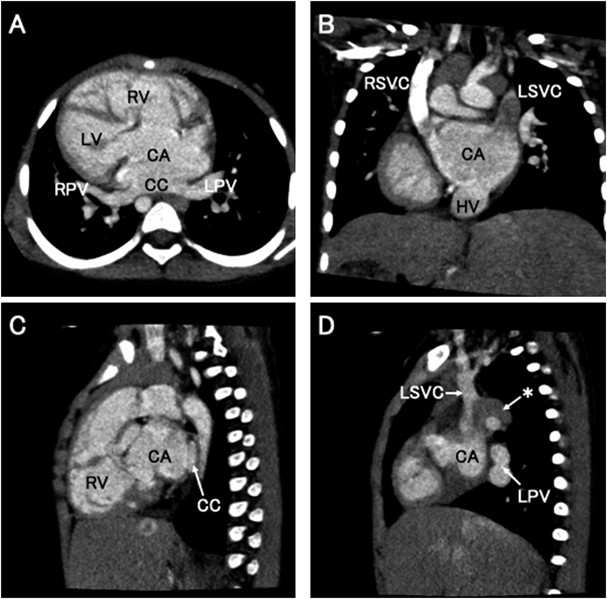

造影CT(Fig. 1)

Pediatric Cardiology and Cardiac Surgery 37(2): 126-132 (2021)

Fig. 1 Preoperative CT images

Patient’s cardiac anatomy presented in the axial view (A), coronal view (B), sagittal view (C and D). Asterisk shows hemiazygos connection. CA, common atrium; CC, common chamber; CT, computed tomography; HV, hepatic vein; LPV, left pulmonary vein; LSVC, left superior vena cava; RPV, right pulmonary vein; RSVC, right superior vena cava.

鏡像型右胸心,単心房,右側大動脈弓を認めた.両側の上大静脈は単心房の左右頭側へそれぞれ接続し,下大静脈欠損で下肢の静脈血流は半奇静脈を介して左上大静脈へ接続,肝静脈は単心房の尾側中央に接続,肺静脈は上下左右四本が共通肺静脈腔を形成して単心房の背側中央に合流していた.右室流出路および肺動脈弁上や末梢肺動脈に狭窄は認めなかった.腹部臓器も逆位であり,右側に胃,左側に肝臓が位置していた.